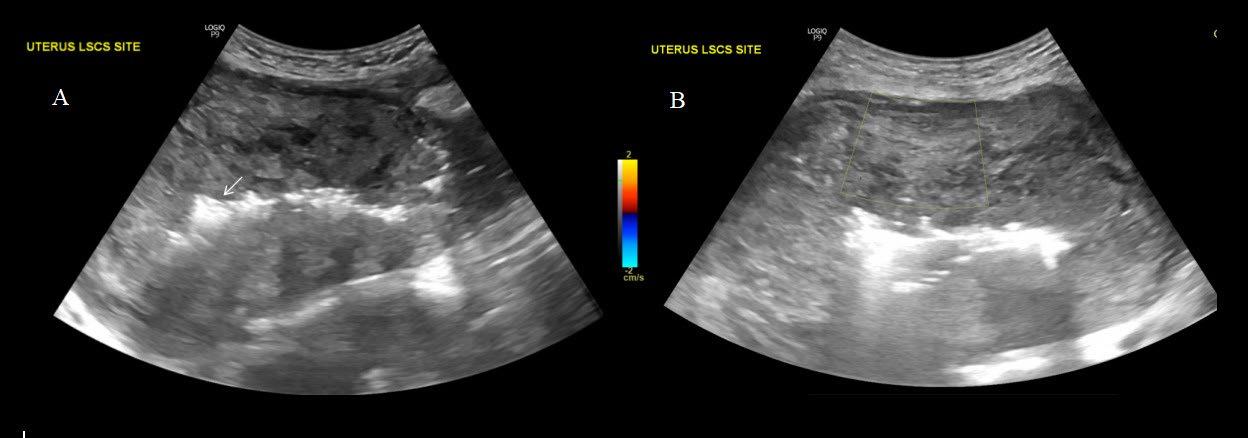

In contrast to acute complications, chronic complications are generally more unique to the Caesarean section itself, and are not typically seen with other surgical procedures, with the exception of incisional hernia. Caesarean scar niche was identified as an important cause of pain and irregular bleeding (Figure 1).

C-section: Caesarean section; US: ultrasound.

A B C D E F G H J K L M I Abstract ● ECR 2024 Creative Commons Attribution-Non Commercial 4.0 ● April 2024 ● Radiology 23

Figure 1: Caesarean scar niche.